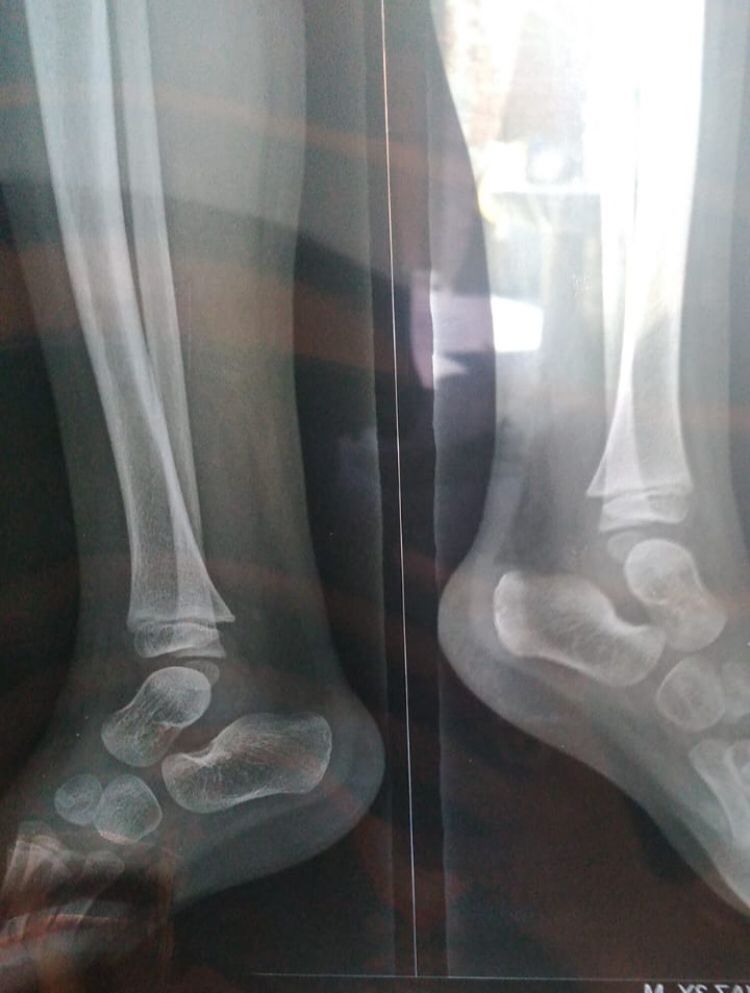

please have look his x-ray

4 years ago

please